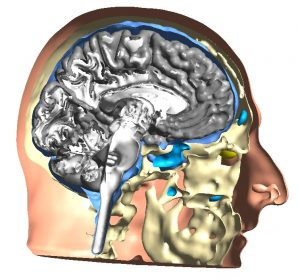

Gdzie w Polsce przeprowadzana jest najskuteczniejsza stymulacja mózgu? Kraków i Sensusmed to miejsce, gdzie jako jedyni w Polsce oferujemy tworzenie modeli mózgu 3D na podstawie obrazów MRI (rezonansu magnetycznego) pacjenta w celu personalizacji i optymalizacji rezultatów terapii stymulacji mózgu. Obok znajduje zdjęcie przedstawiające wygląd takiego modelu.

Gdzie w Polsce przeprowadzana jest najskuteczniejsza stymulacja mózgu? Kraków i Sensusmed to miejsce, gdzie jako jedyni w Polsce oferujemy tworzenie modeli mózgu 3D na podstawie obrazów MRI (rezonansu magnetycznego) pacjenta w celu personalizacji i optymalizacji rezultatów terapii stymulacji mózgu. Obok znajduje zdjęcie przedstawiające wygląd takiego modelu.

Dlaczego warto skorzystać z opcji personalizacji? Działanie w oparciu o indywidualny model mózgu 3D zwiększa celowość terapii, pozwalając znacznie precyzyjniej ustalić lokalizację największego ładunku elektrycznego. Dzięki personalizacji zmniejszamy także ewentualną symulację obszarów niepożądanych – a więc precyzyjnie trafiamy w te obszary mózgu, które powinny zostać poddane stymulacji. Bazowanie na modelu pozwala także na efektywną stymulację kilku obszarów jednocześnie, co zwiększa powodzenie terapii.